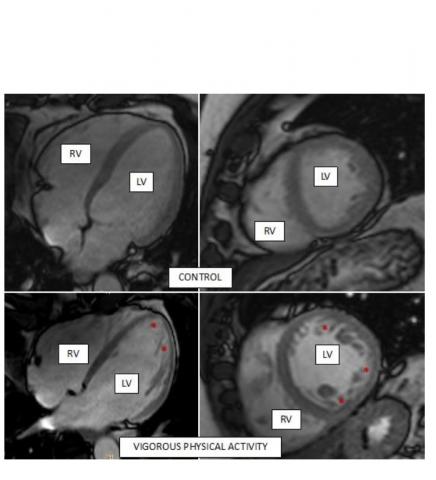

Chez la plupart des sportifs et en particulier chez les athlètes professionnels, le cœur s'adapte à l'entraînement de différentes manières, notamment en augmentant le nombre de ces petit filaments appelées trabécules, essentiels dans l’activité électrique et le fonctionnement du cœur. Chez certaines personnes cependant, cette hypertrabéculation peut devenir pathologique. Les scientifiques du CNIC décryptent le processus sous-jacent à cette hypertrabéculation associée à une « apparence spongieuse » (Voir visuel ci-dessous).

L’équipe du CNIC utilise la résonance magnétique cardiaque pour mesurer l'hypertrabéculation liée à l'exercice chez un groupe de 700 participants à l'étude PESA-CNIC-SANTANDER. Ces participants en bonne santé pratiquaient l’exercice à des niveaux variables, aucun n'était un athlète professionnel. L'activité physique a été évaluée objectivement à l'aide d'accéléromètres portés au cours de périodes d'une semaine coïncidant avec chaque évaluation triennale prévue dans le suivi de l’étude. L'activité physique individuelle a donc pu être classée comme « absente = sédentarité » ou comme exercice léger, modéré ou vigoureux. L’analyse montre que

- les participants avec pratique vigoureuse de l’exercice ont un cœur plus gros avec plus de masse musculaire, des changements « typiques » du cœur sportif ou de l’athlète et considérés comme normaux sur le plan physiologique ;

- 33% des participants ayant un niveau élevé d'activité physique vigoureuse (hommes et femmes) répondent aux critères diagnostiques de la « cardiomyopathie sans compactage », une condition caractérisée par la présence de trabécules « saillantes » alors même qu’ils sont en bonne santé ;